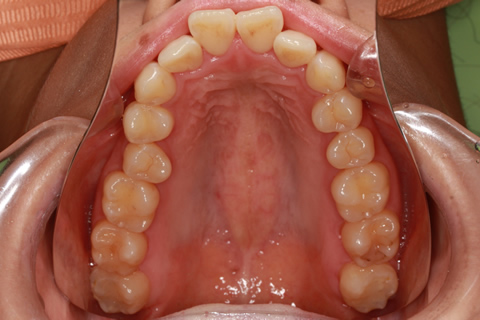

矯正期間24ヶ月

ハーフリンガル矯正3(上の歯のみ舌側矯正で治療)

治療前

治療中(開始直後)

治療中(開始半年後)

治療後

- 年齢・性別

- 25歳女性

- 治療期間

- 2年0ヶ月

- 抜歯

- 上下4番抜歯

- 治療費

- 110万円

- 備考

- 治療内容

- 施術の副作用(リスク)

- 表側矯正と比較して、力学的な操作性が複雑なため、ボーイングエフェクトを起こしやすい。